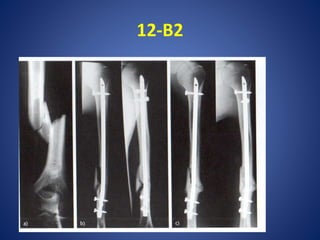

12-B2

• #40 a)Mas 26 años, 12-B2, Sin lesion vascular.b) buena alineacion posterior insercion del clavo con bloqueo estatico.c) 8 semanas ,buen callo ha ponteado los fragmentos principales, asi como el 3 frag Indiscutiblemete , el clavo tambien se puede utlizar